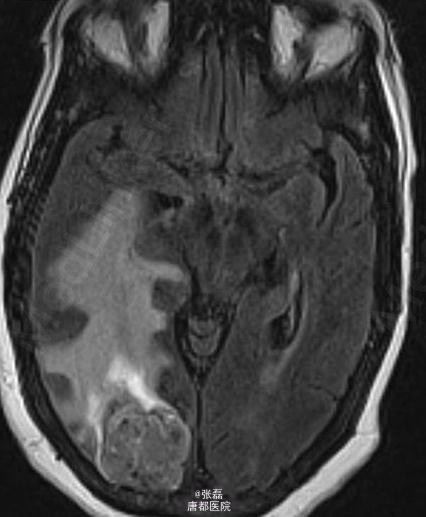

患者女性,63 岁,身体状况下降,在过去几个月期间表现为进展性头痛,无力,步态不稳。

颅脑平扫 CT 显示右侧枕叶肿块,其内密度不均,中间呈低密度。周围脑组织呈血管源性水肿性低密度,邻近脑沟、裂变窄变浅,右侧侧脑室受压变形。 颅脑平扫加强化 MRI 显示:右侧枕叶见一长 T1 等长 T2 异常信号,FLAIR 呈高信号,注入对比剂后呈明显不均质强化,中间呈坏死性不强化改变。病变强化后边界不清,邻近脑实质和后方软脑膜受侵。病变定位脑内,非硬脑膜起源,未见脑膜尾征。周围脑组织可见血管源性水肿征象,累及皮层下和深部白质。MRI 显示较 CT 清晰、明显。 病理诊断:脑转移瘤

大多数伴有脑部转移瘤的患者多采用全脑放射治疗(WBRT),对于单发转移瘤或少数多发也可以考虑手术联合 WBRT 的方式进行治疗。

中枢神经系统以外的恶性肿瘤脑转移最常见方式为血源性播散。